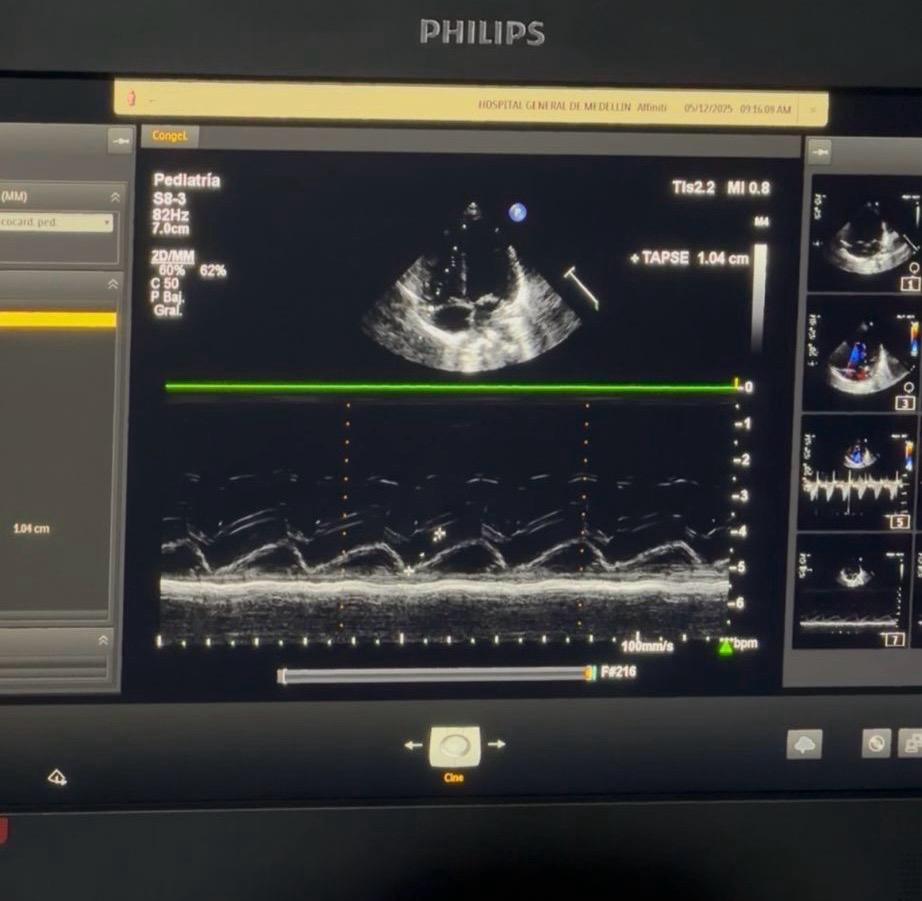

Foto: Caracol Radio.

El Hospital General de Medellín recibió este viernes un ecocardiógrafo pediátrico completamente nuevo, una donación de la Fundación Infantil Santiago Corazón que marca un hito en la detección temprana de cardiopatías congénitas en recién nacidos. Con este equipo, el centro asistencial podrá aumentar de manera significativa su capacidad diagnóstica.

El Hospital General, donde nacen más de 4.000 bebés al año, celebró la llegada del equipo, que además permitirá disminuir los costos operativos: anteriormente el centro debía alquilar un ecocardiógrafo a un costo anual de 120 millones de pesos, sin disponibilidad completa. Con el nuevo equipo propio, los exámenes podrán realizarse sin restricciones de tiempo ni trámites adicionales.